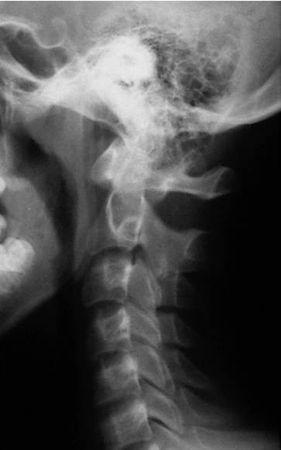

Отсутствие лордоза у детей до 16 лет (рис. 4.8)

Закладка шейного лордоза, как и остальных сагиттальных изгибов позвоночника, происходит во внутриутробном периоде. Возрастной рентгенологической нормы для детей не существует.

Выпрямление сагиттального профиля шейного отдела позвоночника у взрослых является показателем патологии и чаще всего рассматривается как признак болевой контрактуры.

Отсутствие лордоза или легкое кифозирование в среднешейном отделе позвоночника обнаруживается на сагиттальных рентгенограммах в среднем положении головы у 14 % здоровых детей с 8 до 16 лет [7]. Делая заключение необходимо учитывать особенности укладки (рис 4.8 В)!

Для дифференциальной диагностики с травматическими изменениями необходимо произвести рентгенограмму с разгибанием, на которой в случае нормы лордоз восстановится.

Рис. 4.8. Отсутствие лордоза у детей до 16 лет А – нормальный лордоз у подростка 14 лет.

Б – боковая рентгенограмма здорового ребенка 9 лет. Прямой сагиттальный профиль. Вариант нормы.

В – пологое кифозирование на уровне CII–CV у ребенка 6 лет. Снимок сделан лежа – видна поверхность стола, и голова наклонена вперед. Сагиттальный профиль связан с особенностью укладки